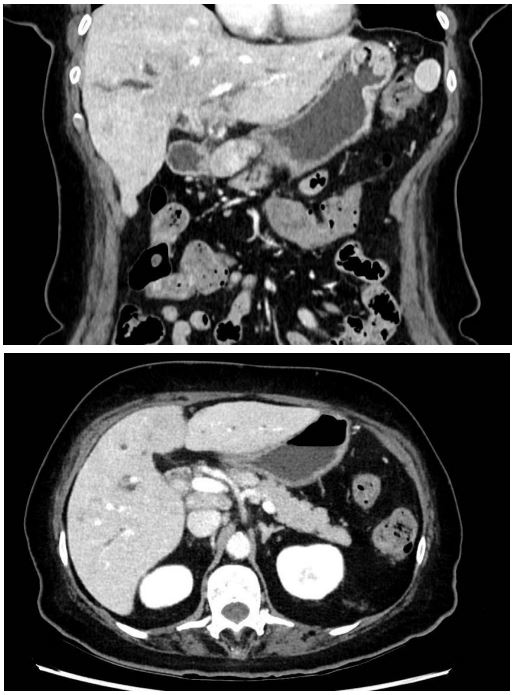

Computed tomography of the chest and abdomen disclosed pathological contrast and wall thickening of the proximal bile duct and right hepatic duct. The left hepatic duct was no longer visible due to diffuse tumor infiltration of the central hepatic parenchyma resulting in dilatation of the intrahepatic bile ducts. A complete occlusion of the biliary convergence with complete separation of the bile ducts to the 2nd convergence was observed. In addition, multiple adenopathy of the hepatic hilum, celiac, gastric greater curvature and retroperitoneal and cardio-phrenic were visible (Figure 1). Magnetic resonance imaging confirmed the CT findings with additional intrahepatic, vertebral body metastases and multiple pulmonary nodules (Figure 2).

Figure 1: Thoraco-Abdominal CT scan.